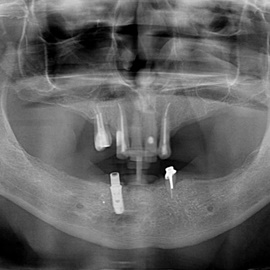

Lat 50, pół roku przed rozpoczęciem leczenia implantologicznego przestał palić papierosy. Znacząca poprawa higieny, pacjent silnie zmotywowany. Po regeneracji kości i rekonstrukcji tkanek miękkich odbudowa sześciu zębów na koronach porcelanowych. Na zdjęciu widoczna ilość i jakość tkanki kostnej po rekonstrukcji. W porównaniu ze stanem początkowym uzyskano znaczącą poprawę warunków kostnych nie do osiągnięcia metodami sterowanej regeneracji kości z użyciem reklamowanych markowych błon kolagenowych i dosypaniem kości z butelki.

Pacjent z długą historią leczenia implantologicznego. Pierwsze implanty w pozycjach 23, 24 miał wkręcane w Warszawie przed 25 laty. Implant w pozycji górnego prawego kła ma agresywny gwint, ponieważ bezpośrednio po implantacji był obciążony (immediate loading) tymczasowym atachmentem ball abutmentv do stabilizacji tymczasowej protezy ruchomej. Kość szczęki regenerowana i odbudowywana etapami w całym górnym prawym kwadrancie. Pacjent planuje uzupełnić brakujące zęby 25, 26.

Pacjentka lat 72, od kilkudziesięciu lat chorująca na cukrzyce I typu, obecnie od 10 lat na pompie insulinowej. Profesor medycyny, siostrzenica pacjentki prowadzi swoją ciocię diabetologicznie, pacjentka świadoma zagrożeń przy zabiegach regeneracji kości i implantacji w takim ogólnym stanie zdrowia. Po rekonstrukcji tkanek miękkich i kości osadzono dwa implanty o średnicy 5,0 mm. Na zdjęciu śródzabiegowym widać zadowalające wyniki rekonstrukcji tkanki kostnej. Po upływie kilku miesięcy wykonano nadbudowę protetyczną.

Pacjentka po ekstrakcji kilku zębów, z implantacją natychmiastową, odroczoną. Zdjęcie pantomograficzne wykonano pięć lat po implantacji. Widoczna stabilna sytuacja kostna i dziąsłowa.